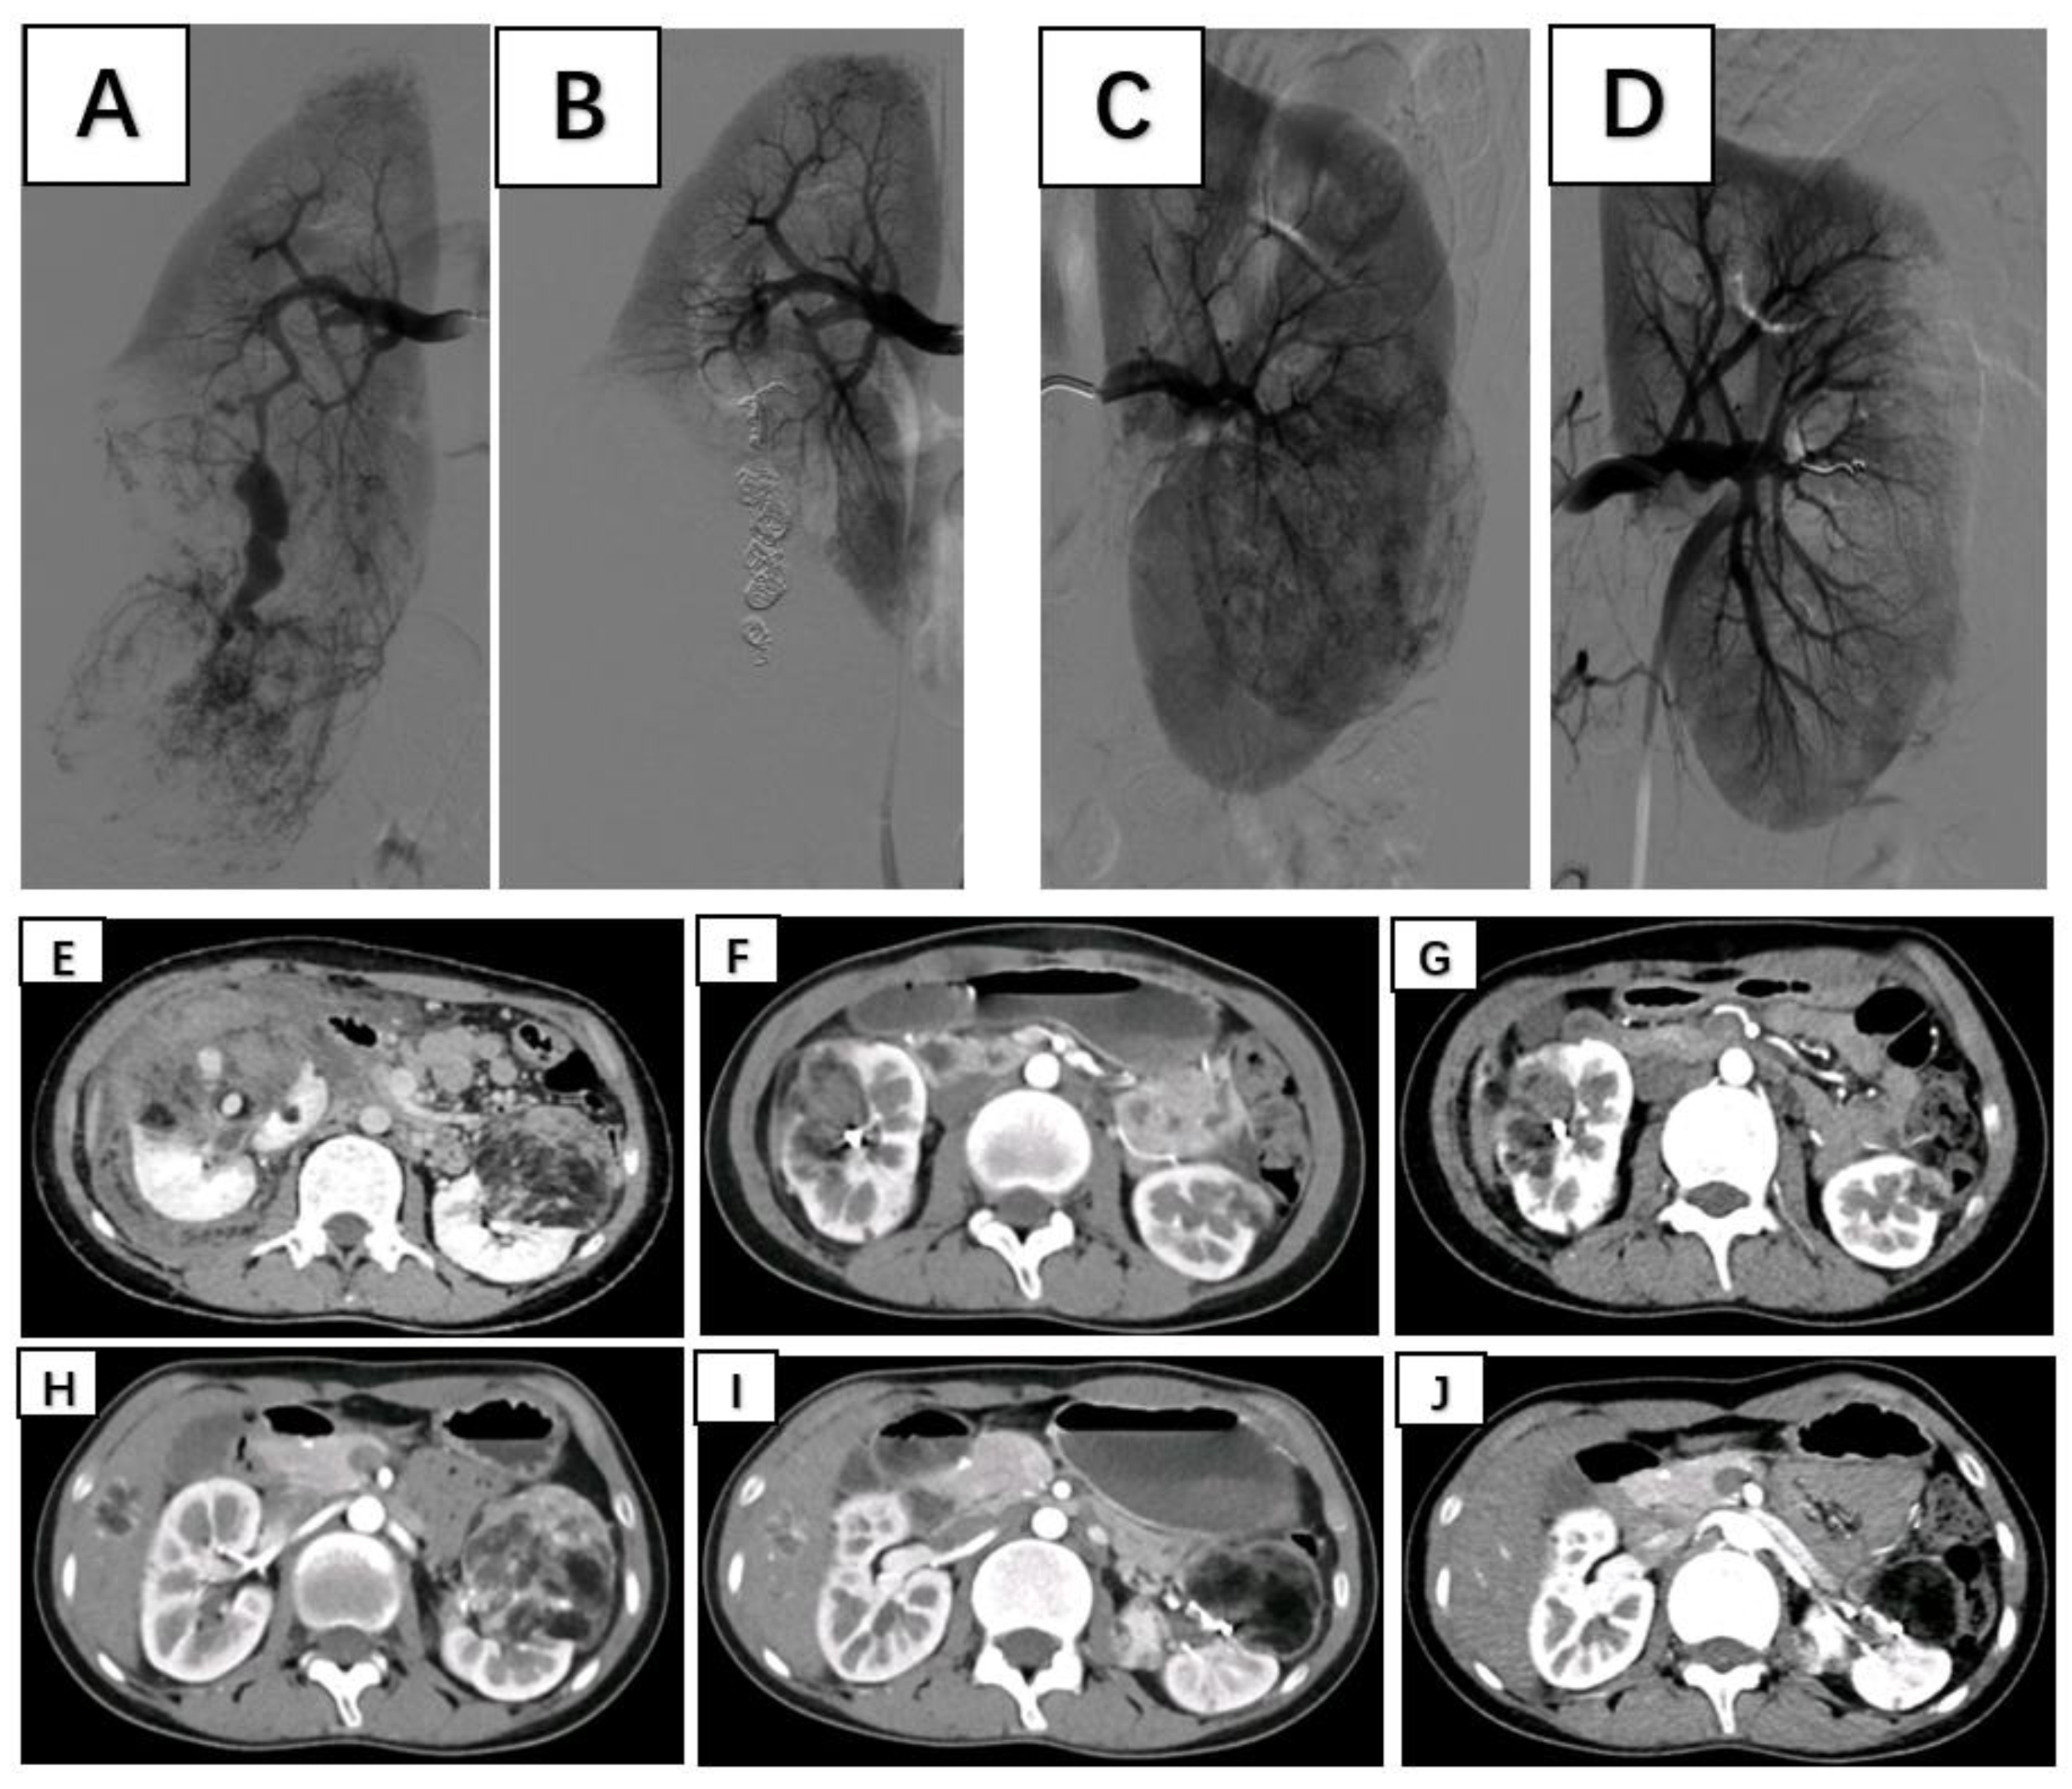

Figure 1. A-B: Immediate pre- and postembolization imaging of the right renal angiomyolipoma; C-D: Immediate pre- and postembolization imaging of the left renal angiomyolipoma; E-G: Rupture and hemorrhage of the right renal angiomyolipoma, followed by 6-month and 12-month follow-up contrast-enhanced CT showing a significant reduction in tumor size; H-G: Preembolization, 3-month postembolization, and 6-month postembolization follow-up contrast-enhanced CT images of the left renal angiomyolipoma demonstrating a marked reduction in tumor size.

Patients were placed in the supine position and routinely disinfected and toweled. The right common femoral artery was used as the puncture point for all patients. Local anesthesia with 1% lidocaine was administered, and the modified Seldinger method was used for retrograde puncture of the right femoral artery. After successful puncture, a 6F sheath (Cordis, USA) was inserted under the guidance of a 0.035 inch×150 cm guidewire (ZIPwire, Boston Scientific), and a 5F PIG (Cordis, USA) catheter was advanced to the upper segment of the abdominal aorta. High-pressure injection angiography is performed to locate the opening of the renal artery and determine the number, morphology, and lesion location of the renal arteries, followed by selective renal arteriography. Under the guidance of a 0.035 inch×150 cm super smooth guidewire, a 5F C2 catheter (Cordis, USA) was advanced to the opening of the diseased side renal artery. Renal artery openings were localized using high-pressure syringe angiography to determine the number, morphology, and location of the renal arteries. Depending on the size of the target vessel diameter, microguidewires (Asahi Intecc Co., Ltd.) are used to guide the insertion of either a 1.98Fr or 2.6Fr coaxial microcatheter (Microcatheter, Asahi Intecc Co., Ltd.) into distal branches at levels two or three in the renal artery. High-pressure injection angiography again revealed signs such as direct bleeding from the extravasation contrast agent and tortuous enlargement with structural disorder along with vascular composition outlining tumor contours in blood supply arteries feeding into tumors. After careful assessment of the tumor’s blood supply, a suspension of polyvinyl alcohol (PVA) embolic agent (COOK, USA) mixed with an appropriate amount of contrast agent (usually at a concentration of 30% to 40%) was prepared. Under vascular angiography and fluoroscopy, the PVA particle suspension is injected into the tumor-feeding artery through a microcatheter at an appropriate speed to avoid reflux. For patients with concomitant arterial aneurysms, embolization coils (COOK, USA) of suitable diameter and quantity are used for embolization based on the target vessel diameter. For patients without arterial aneurysms, if incomplete embolization is observed after the use of PVA particles, spring coils are used to embolize the main tumor-feeding artery. In cases where the tumor is supplied by multiple arteries, selective embolization of each branch vessel with appropriately sized PVA is performed to minimize damage to normal renal units. Subsequent DSA revealed no distal visualization or extravasation of contrast agent in the branch vessels supplying the renal tumors. The right femoral artery puncture site was closed using a vascular closure device followed by hemostatic compression and pressure bandaging. After completion of the procedure, the patient returned to the ward for bed rest with immobilization of the right lower limb for 24 hours while closely monitoring for any signs of bleeding from the puncture site. (Figure 1)

5. Follow-up

The average follow-up period after surgery for both groups of patients was 22 months, and all patients received outpatient follow-up. In the SAE group, postembolization re-examination via bilateral renal CT revealed a significant reduction in tumor diameter, indicating remarkable therapeutic efficacy. During the follow-up period, neither group underwent further surgery, and there was no tumor recurrence. In the SAE group, the average tumor diameter decreased by 3.33 cm compared to that in the preembolization group (P<0.05) (Table 4).